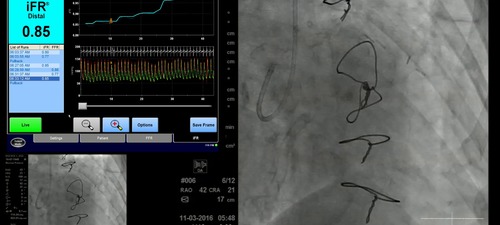

Physiology data is interpreted by the live case operators and the expert panel

The live case team discuss the interpretation of anatomical and physiological data to plan revascularisation strategy.

• Use of iFR to assess ischaemia

• Use of iFR-Scout to map out physiological gradients along the lengh of the vessel